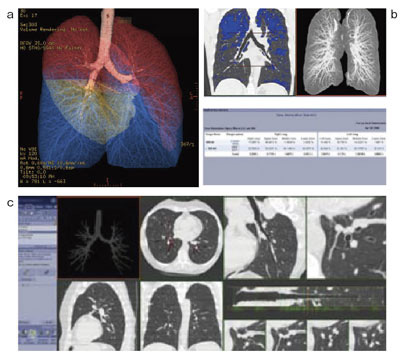

肺野専用アプリケーションThoracic VCARでは,COPD(慢性閉塞性肺疾患)に代表される肺気腫や気管支解析をサポートする。肺気腫解析は,肺野内の低吸収領域の体積が表記され,上中下葉のセグメンテーションをあらかじめ行うことで各葉ごとの値を得ることもできる。気管支解析は,自動的に気管支のみの3D画像が表示され,関心のある気管支をワンクリックすることで,その展開像や気管支に沿った断面を観察でき,気管支の壁厚や内腔面積などを計測可能である(図3)。

図3 Thoracic VCAR

a:上中下葉にセグメンテーションした肺のVR像

b:肺気腫解析の画像と体積表記

c:気管支解析の全体画面